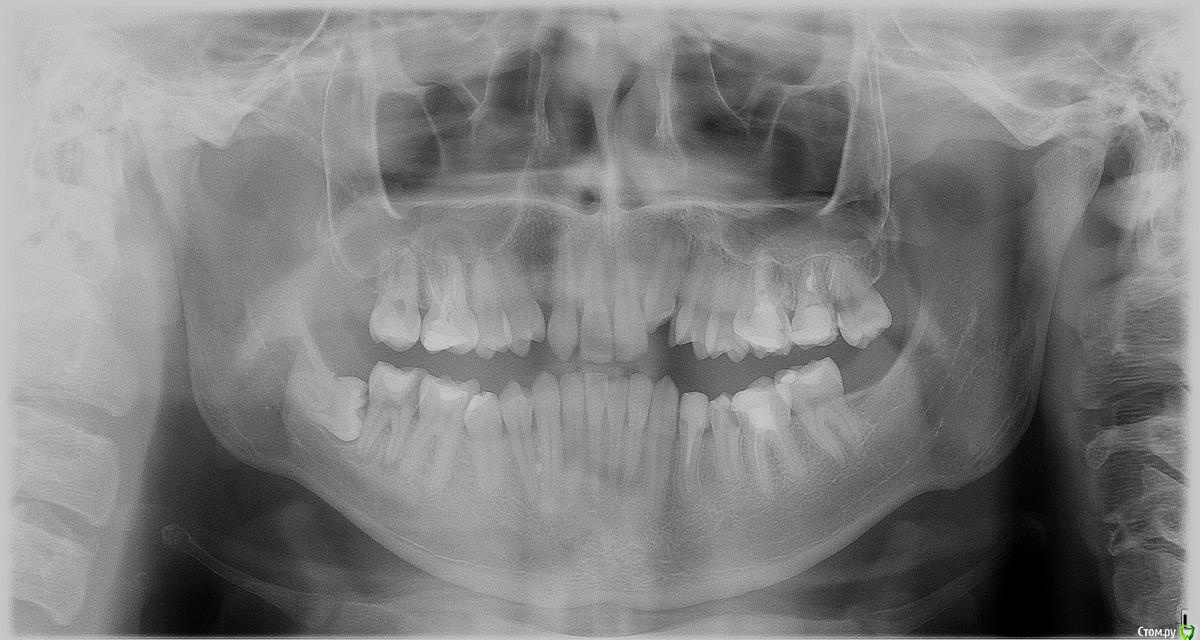

newuser Опубликовано 17 июня, 2018 Поделиться Опубликовано 17 июня, 2018 Ортодонт сказал что нужно удалить зуб сверху, и если есть зуб мудрости предлагают удалить именно его тк рудимент. Но ведь если его передвинуть в нем будет смысл. На восьмом недавно появился кариес, но в то же время шестой визуально в очень плохом состоянии - часть желтая шероховатая, видимая линия вокруг пломбы, весь зуб розовый. Какой зуб удалять? 1) Удалить восьмой и восстановить шестой (хотя я даже не знаю возможно ли восстановить зрительно настолько разрушенный зуб, тем более моляр (предполагал винир) 2) Удалить шестой, вылечить кариес на восьмом и передвинуть восьмой и седьмой на места седьмого и шестого соответственно Ссылка на комментарий

сирена Опубликовано 18 июня, 2018 Поделиться Опубликовано 18 июня, 2018 Восьмой удаляйте,передвинуть не получится. Ссылка на комментарий